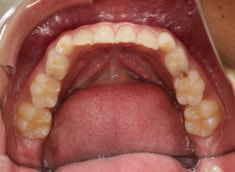

治療後(1年1ヶ月後)